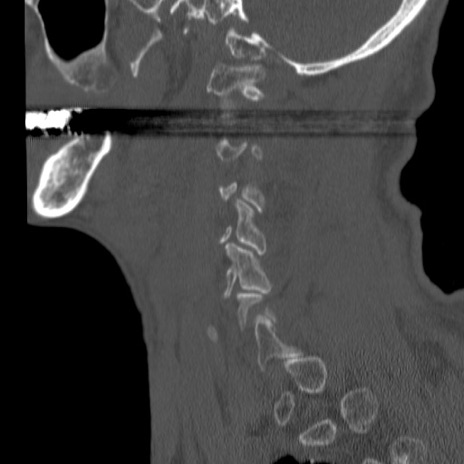

症例46 頚椎CT(矢状断像)

【症例】80歳代男性

【主訴】両側頚部〜上肢のしびれ

【現病歴】昨日、自宅内で転倒、その後より上記症状あり。意識障害なし。

【身体所見】両側上肢のallodynia(熱痛覚過敏)あり。MMTおよびDTRは正確な所見取れず。両上肢の挙上はなんとか可能。

異常所見と診断は?